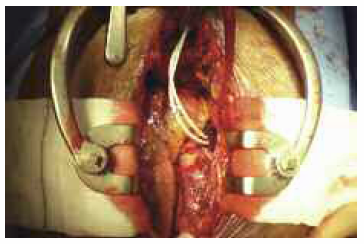

At CABG, there was a large aneurysm of the aortic root. A left internal mammary artery graft to the left anterior descending coronary artery was performed off pump. Two 4-0 Prolene purse-string sutures were inserted into the right atrial appendage before inserting each Tesio line. The purse-string sutures were secured individually, with progressive invagination of the surrounding atrial appendage tissue. The lines were tunneled following the pleural-pericardial reflection, with an exit site in the upper abdominal wall just below the costal margin (Figure 2). Correct positioning was confirmed at the time of insertion using image intensification.

Figure 2. Intra-atrial dialysis line inserted during CABG.